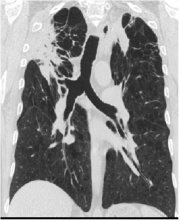

| 08:28, 5 במרץ 2015 | COPD1.jpg (קובץ) |  |

40 קילו־בייטים | Motyk | שוחזר לגרסה מ־11:21, 16 ביולי 2012 | 2 |